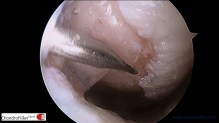

– ΣΥΝΔΕΣΜΟΠΛΑΣΤΙΚΗ ΠΡΟΣΘΙΟΥ ΧΙΑΣΤΟΥ ΣΥΝΔΕΣΜΟΥ ΜΕ ΤΕΧΝΙΚΗ ALL-INSIDE